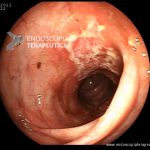

Colite por Doença de Crohn

- Doença de Crohn em atividade leve